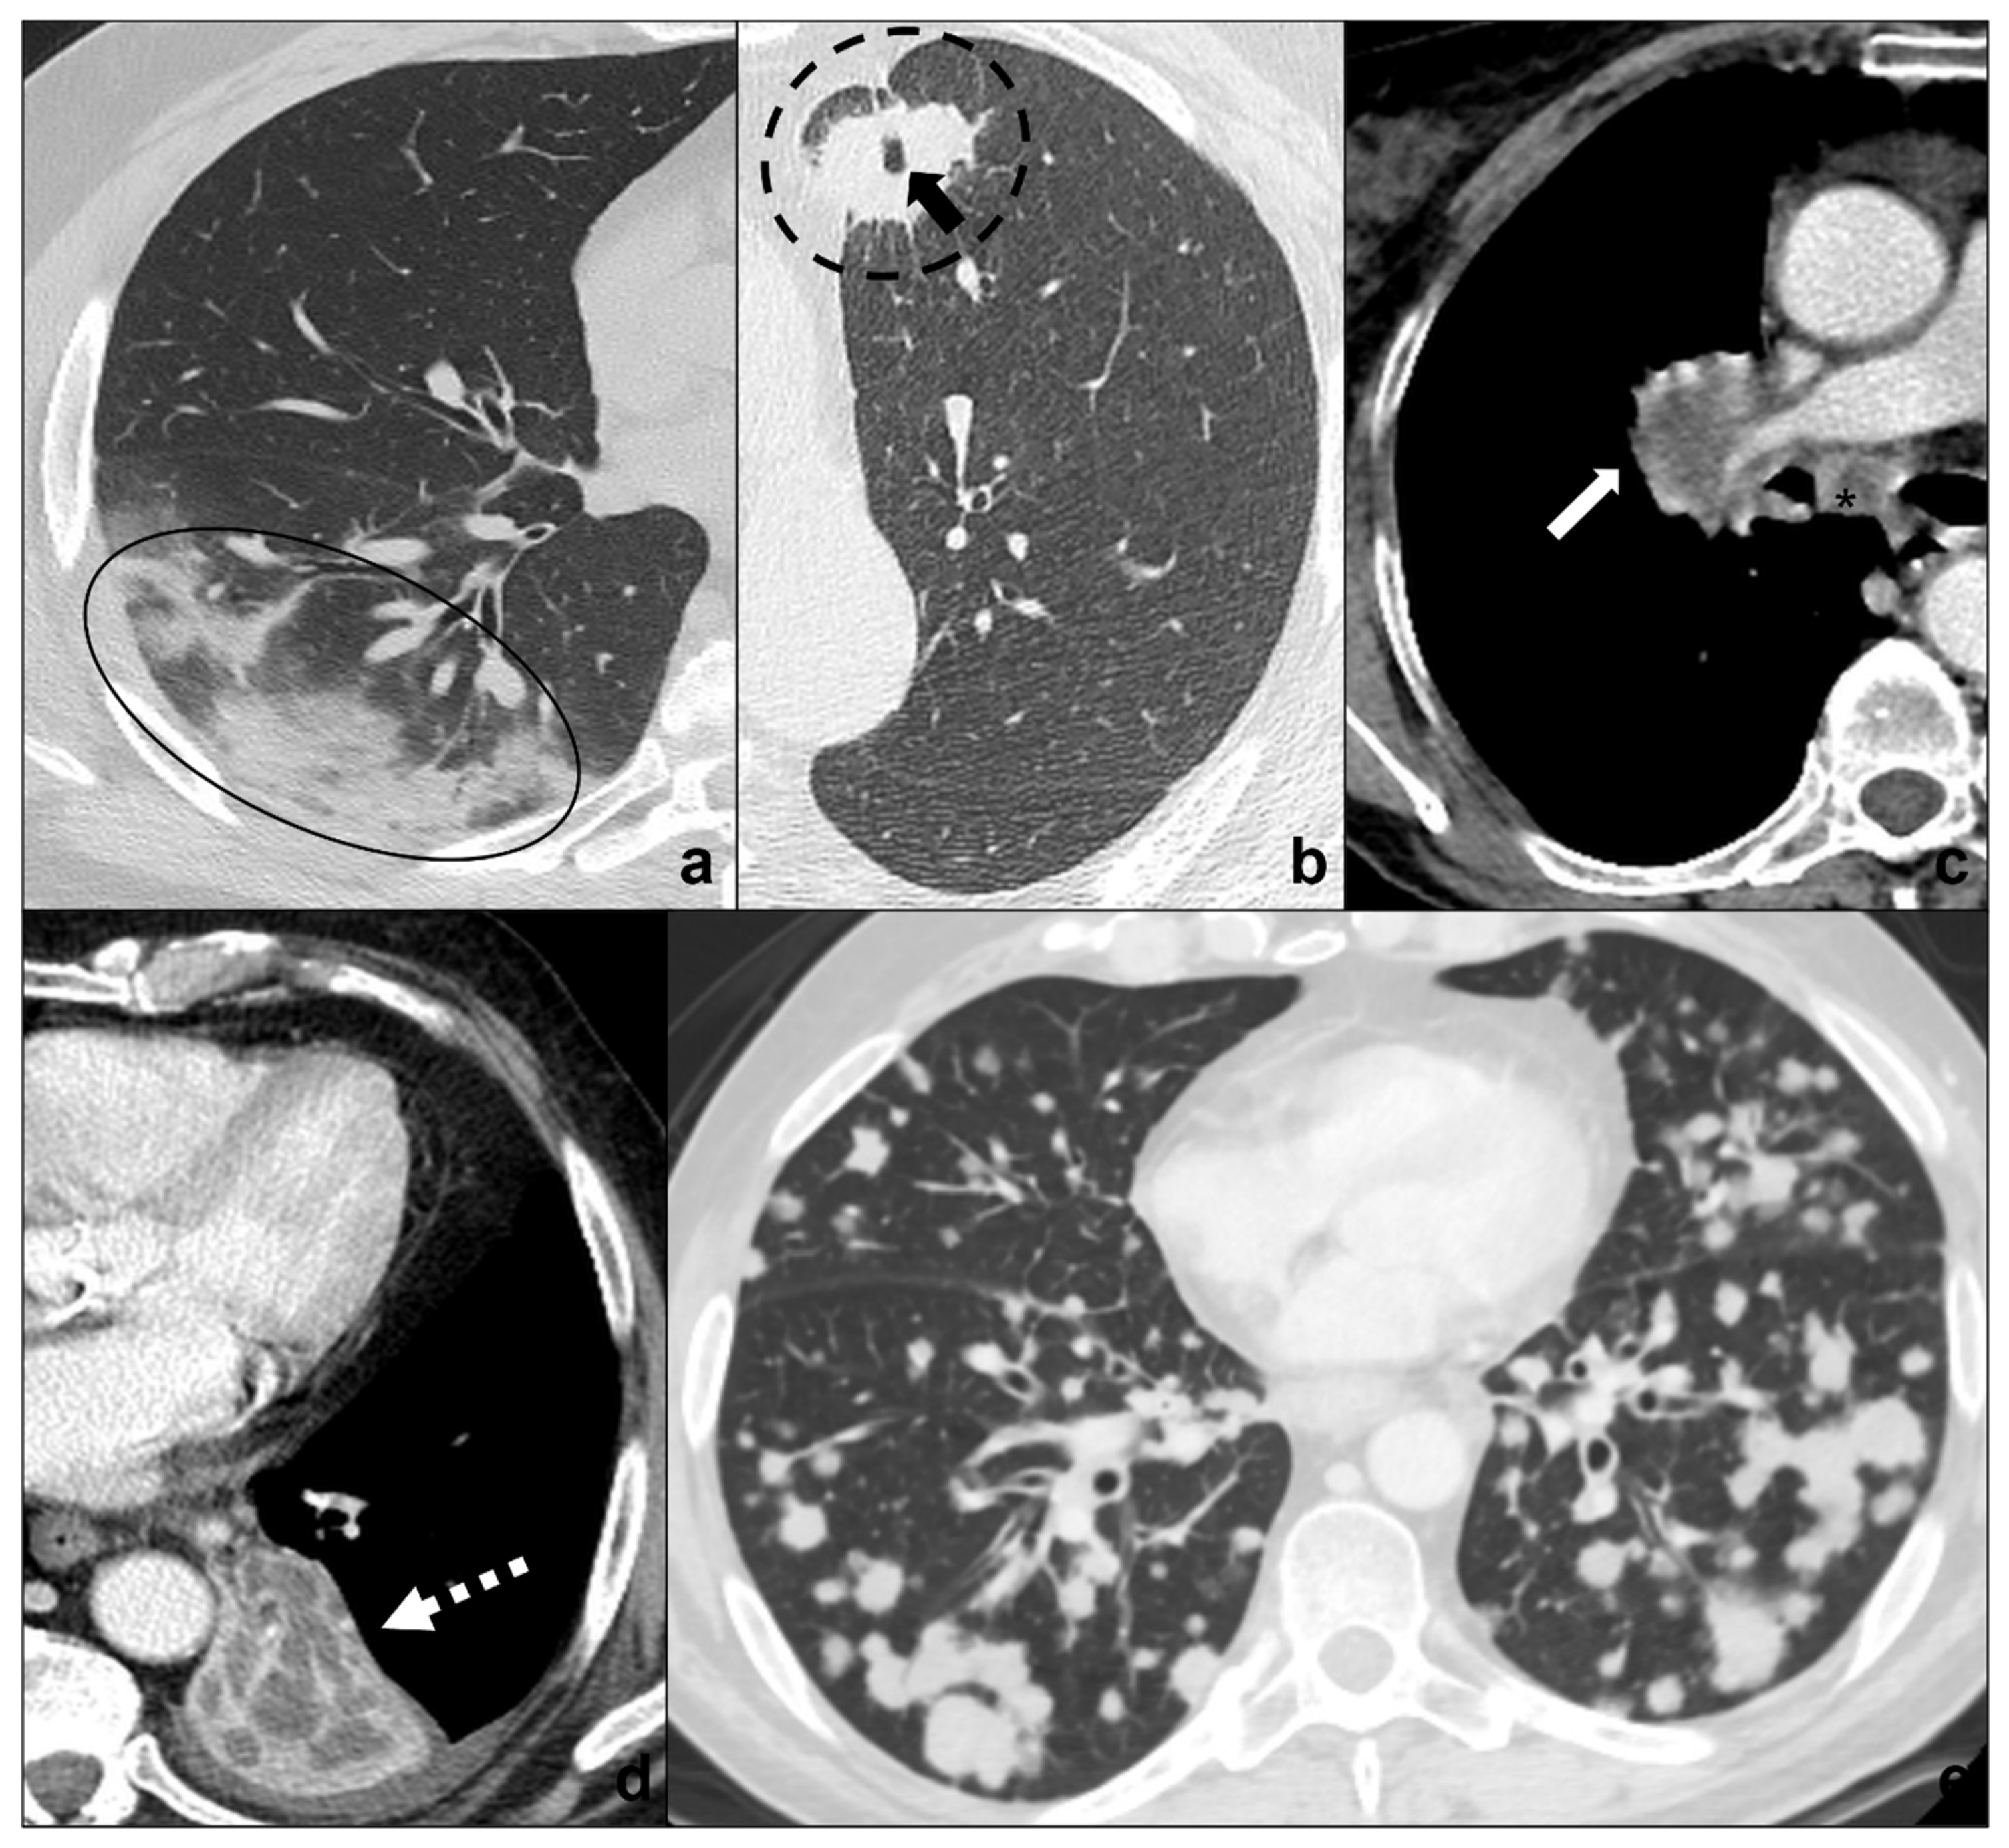

Figure 5.

(a–e) Chest CTs showing differential diagnoses of COVID-19 pneumonia stage 3/consolidations. Subpleural ill-defined consolidations are typical of COVID-19 pneumonia stage 3 (black circle) and are generally easy distinguishable from lung cancer, especially if lung tumors present as big masses with spiculated margins, pleural retraction striae (dotted black circle in (b)), cavitations (black arrow in (b)) and lymphadenopathies (black asterisk in (c)). Contrast administration is useful to appreciate the inhomogeneous enhancement of lung tumor and mediastinal tissue infiltration (white arrow in (c)), and/or additional findings such as lobar atelectasis (dotted white arrow in (d)) secondary to bronchial invasion with progressive lobar hypoventilation and secretive stagnation. Solid metastases (e) may be differentiated by COVID-19 consolidations because they appear as roundish nodules with regular margins and a random distribution in relation to hematogenous spread. Lungs: mean window with 1500 HU; mean window level −600. Mediastinum: mean window with 350 HU; mean window level 50 HU.

- generally focal entities, appearing as a single nodule (<3 cm) or mass (>3 cm) with invasive and infiltrative features;

- spiculated margins with pleural and parenchymal retraction stripes causing extensive pulmonary distortions and mediastinal attraction;

- inhomogeneous density in relation to hemorrhagic and/or necrotic foci (e.g., small cell carcinoma, large cell carcinoma);

- inhomogeneous contrast enhancement that is typical of cancer and is not seen in COVID-19 consolidations;

- possible endobronchial growth and spread through airspace (STAS), which has been recognized as a feature with prognostic significance in 2021 WHO classification of thoracic tumors;

- not generally associated with ground-glass or crazy paving areas. If ground-glass or crazy paving areas are present due to edema and hemorrhage, they do not follow COVID-19 pneumonia phases;

- may be central or peripheral, but do not present a strictly subpleural distribution (squamous cell carcinoma and small cell carcinoma being generally central tumors whilst large cell carcinoma being often peripheral);

- grow during antibiotics/anti-inflammatory therapies;

- cysts and/or cavitations (squamous cell carcinoma);

- chest wall, mediastinum and mediastinal organs invasion (frequent in small cell carcinoma, which is most common oncological cause of superior vena cava compressive/infiltrative/thrombotic obstruction);

- associated findings such as atelectasis (Figure 5d) and post-obstructive pneumonia (typical of endobronchial growing tumors such as squamous cell carcinoma;

- lymphangitis carcinomatosis;

- mediastinal lymphadenopathies and pleural effusions;

- systemic metastasis, which are particularly early and frequent in small cell carcinoma.

3.4.2. Multiple Consolidations

Metastases

Metastases are multiple parenchymal and/or pleural lesions secondary to a primitive cancer. Solid metastases present as solid, homogenous nodules with random distribution, regular margins, and nodular morphology, even if there are rarer and atypical presentations [37,38,49].

Anamnesis and clinical signs and symptoms are crucial for the suspicion of solid lung tumors. Radiological features for differential diagnosis of multiple consolidations and COVID-19 pneumonia [38,39,49] (Figure 5a,e):

- generally present as discrete regular nodules with roundish morphology while COVID-19 consolidations present ill-defined margins and do not show a nodular appearance;

- generally present a random distribution in case of hematogenous spreading or may present a spreading through airspace (STAS);

- may be asymptomatic and increase in number and dimensions during antibiotic and anti-inflammatory treatment;

- are not frequently associated with ground-glass or crazy paving opacities and do not follow COVID-19 pneumonia phases.